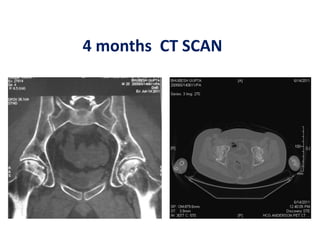

4 months CT SCAN

342 patients (534hips) with Avascular Osteonecrosis at early stages (Stages I and II) Treated with core decompression and autologous bone marrow grafting obtained from the iliac crest Patients were followed up from 8 to 18 years.

69 hips withstage I osteonecrosis demonstrated total resolution of osteonecrosis based on pre and postoperative MRI studies For the 371 other hips without collapse at the most recent follow up (average 12 years), the abnormal signal persisting was seen on T1 images as intralesional area of low intensity signal with a disappearance of marginal band like pattern. THR was necessary in 94 hips

Best indication forthe procedure is symptomatic hips with osteonecrosis without collapse. Patients who had the greater number of progenitor cells transplanted in their hips had better outcomes.